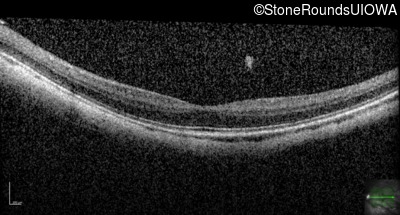

Age at visit: 17 years

OD OS